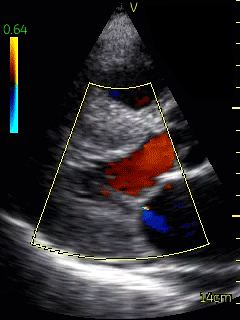

A bedside echocardiogram (VScan, GE) showed evidence of severe left ventricular and right ventricular thickening. Both atria were severely dilated. The mitral, tricuspid, and aortic valves appeared thickened. Myocardial speckling was not appreciated. Both the left and right ventricular function appeared to be moderately impaired.